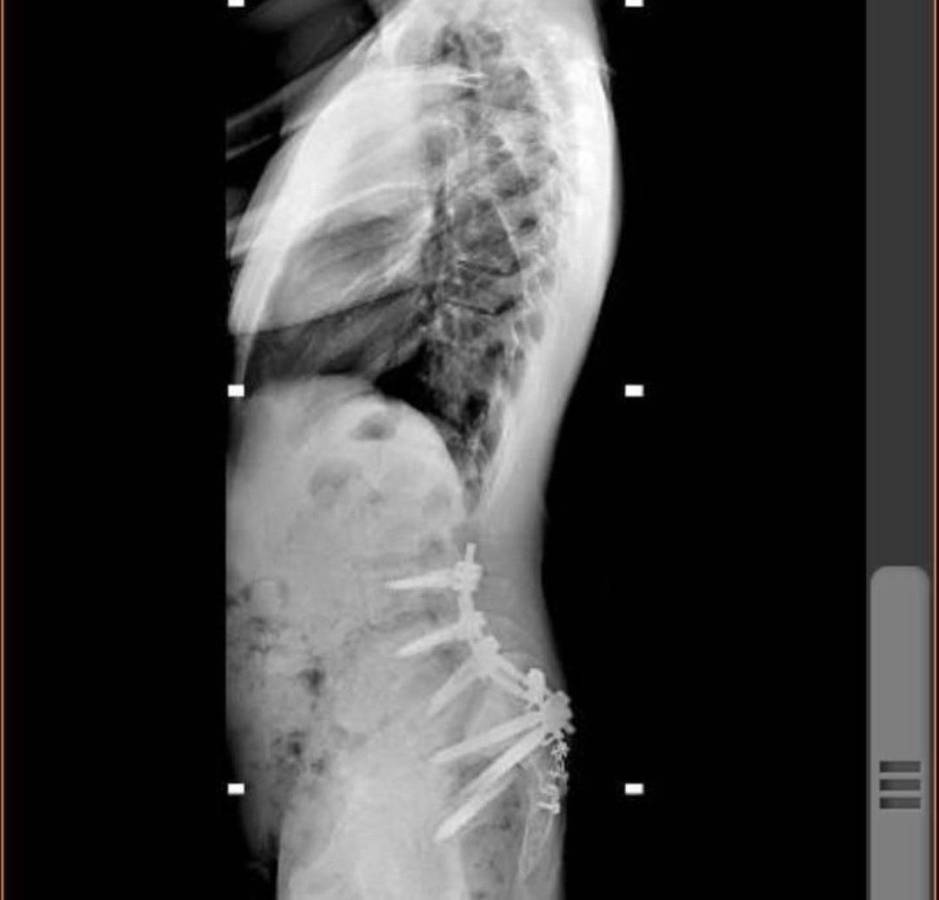

A través de su cuenta de Instagram, el joven compartió una serie de fotografías de los momentos más significativos tras el aparatoso incidente.

Michel relató que después de impactar contra el suelo a +100km/h, lo que más recuerda es que no podía mover el cuerpo desde el pecho hasta los pies.

“Después de una semana en Rhode Island, el doctor Ziya Gokaslan, todo su equipo y yo estábamos listos para ir al quirófano para arreglar lo que pudiera arreglarse. Cuando me abrieron la espalda solo me encontraron un nervio sacro roto. Fue entonces cuando las cosas dieron un giro drástico al convertir una cirugía de 16 horas en una cirugía de 6 horas y la noticia de que iba a poder caminar de nuevo”, narró.